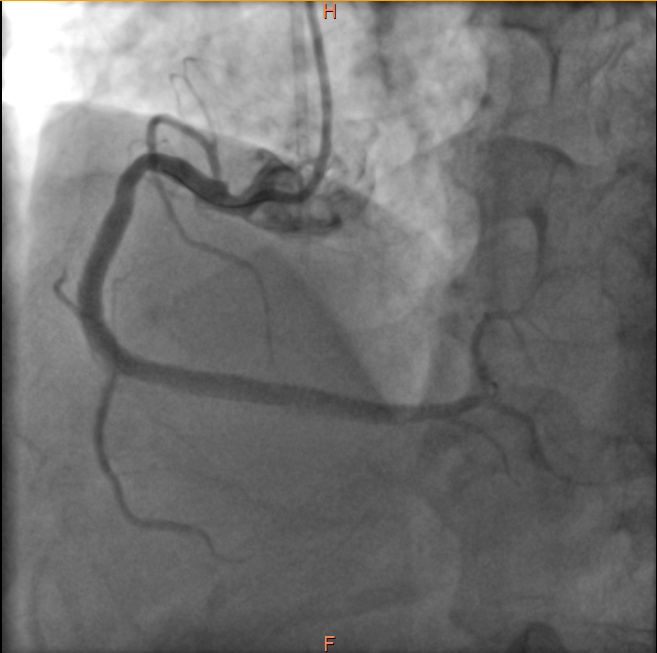

虽然如此,病人右冠状动脉的危险情况仍未完全解除,如同达摩克利斯之剑悬在头顶,不知未来哪天还会再发心肌梗死。经过心内科医师与患者家属的积极沟通解释,几日后再次送至导管室,于右冠状动脉病变处植入了心脏支架,保障了血流通畅。

介入术后的右冠